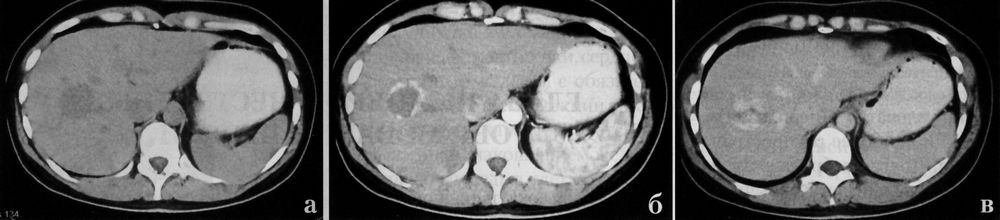

Кавернозная гемангиома печени в своей структуре может содержать бесформенные участки с более низким денситометрическим показателем, что является отображение гиалиноза и дегенеративных изменений. По этим причинам большие гемангиомы требуют дифференциальной диагностики с другими образованиями (гепатомой). Фиброзные рубцы в кавернозных гемангиомах придают опухоли пестрый вид (фото КТ выше). Зона краевого накопления расширяется по направлению к центру, поскольку кровь внутри гемангиомы медленно течет от периферических синусов к центральным. Максимальное контрастирование наступает в поздней паренхиматозной фазе, когда опухоль окрашивается полностью. На томограммах гемангиомы печени при адекватном контрастировании выглядят как гиперденсивные образования, в силу накопления контрастного вещества интерстициальным компонентом опухолевой ткани. Это очень специфичный признак гемангиомы печени. К сожалению, описанную выше перфузию с центростремительным усилением и поздним заполнением показывают, примерно, 54% гемангиом.